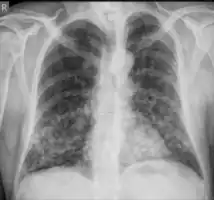

Chest X-ray: Nodular shadows both lungs

In the juvenile form, lung abnormalities are shown in high-resolution CT scans of the lungs, whereas in the chronic form plain X-rays may show interstitial and alveolar infiltrates in the central and lower lung fields.[14]